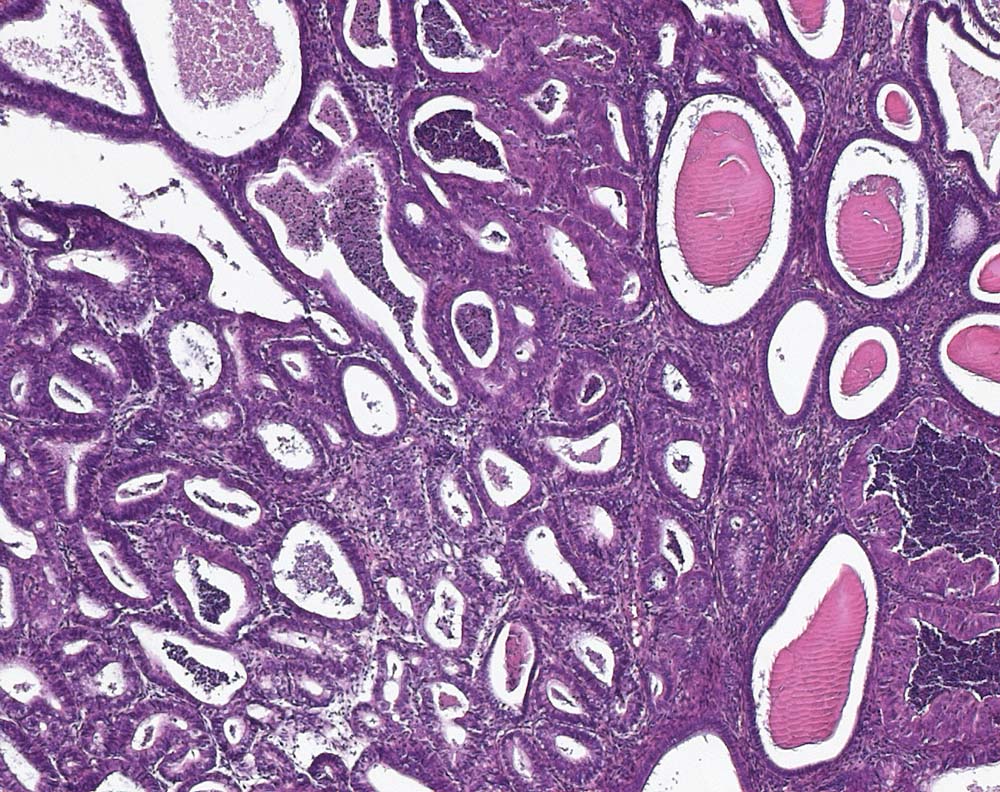

PathoPic – image database / PathoPic ID 10369 - Endometriale intraepitheliale neoplasie (EIN)

Endometriale intraepitheliale neoplasie (EIN)

maligner Tumor

Endometrium

Endometriale intraepitheliale Neoplasie: Umschriebener Herd sehr dicht beeinanderliegender Endometriumdrüsen ausgekleidet von atypischem Epithel, welches sich zytologisch deutlich vom Epithel der nicht neoplastisch transformierten Drüsen unterscheidet. Im Gegensatz zum endometrioiden Adenokarzinom ist zwischen den Drüsen der EIN noch wenig Stroma erkennbar.

Endometriale Hyperplasie, Verdacht auf Neoplasie im Uteruskorpus. Postmenopausen-Blutung.

Histologie

100